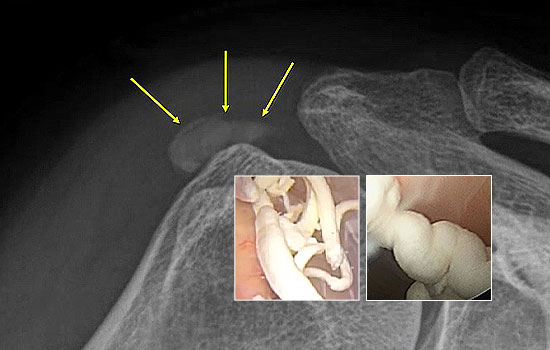

어깨의 석회는 그 시기에 따라 액체형과 고체형 그리고 혼합형으로 존재할 수 있습니다.

액체형 석회를 흡인하는 것은 어디에서나 가능합니다. 하지만 고체형 그리고 혼합형 제거에는 많은 노하우가 필요합니다.

서울거탑정형외과에서는 고체형 석회를 잘게 분쇄하여 뽑아내는 독자적인 기술과 노하우를 보유하고 있습니다.

형성기/휴지기의 고체형 석회

흡수기의 액체형 석회

해당 시술은 석회의 위치를 초음파로 정확히 확인한 뒤,정교한 기술로 진행되는 비수술 치료입니다.

그만큼 의료진의 숙련도와 경험이 매우 중요하므로, 풍부한 시술 경험을 가진 정형외과 전문의를 통해 치료받는 것이 좋습니다.

서울거탑정형외과에서는 풍부한 노하우로 초음파를 통해 정확히 석회를 확인 후 고체형일지라도 미세하게 분쇄하여 제거가 가능합니다.

95%이상 석회 제거가 가능합니다.